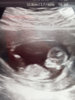

Ensi viikon lopulla päästään uudelleen ultraan, koska nyt ei saatu viikkojen takia mitattua niskaturvotusta.